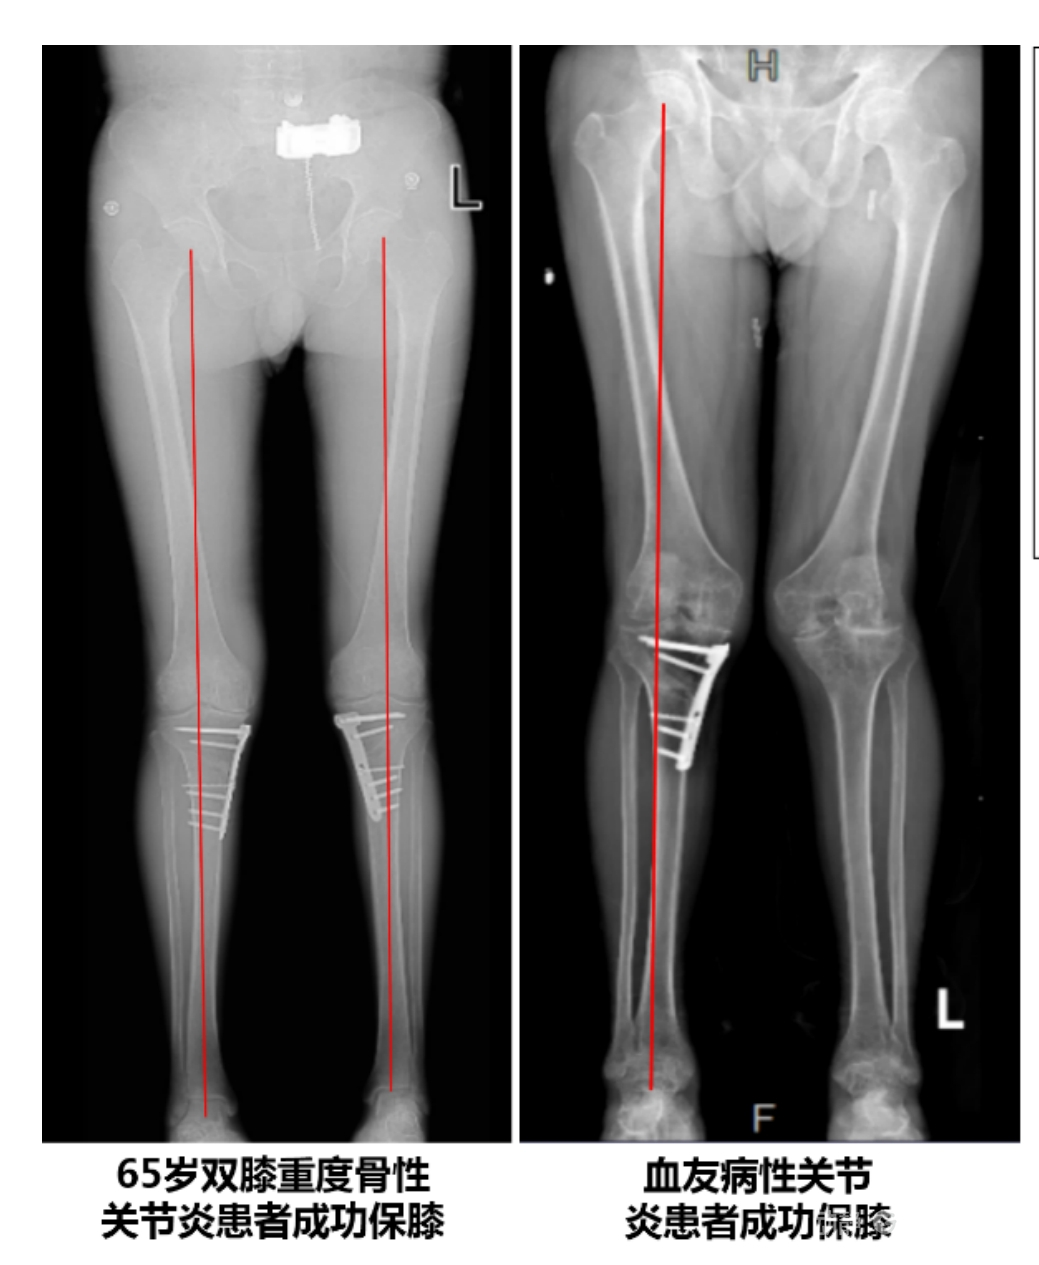

4.2 APTT-HTO脛骨高位截骨術(shù)

2025年7月,貴州醫(yī)科大學(xué)附屬醫(yī)院骨科團(tuán)隊(duì)原創(chuàng)研發(fā)的腘肌前結(jié)節(jié)中脛骨高位截骨保膝術(shù)(Anterior Popliteus Transtibial Tuberosity-High Tibial Osteotomy, APTT-HTO)及其提出的脛骨結(jié)節(jié)分區(qū)與腘肌保護(hù)理論,登上了國際頂尖學(xué)術(shù)舞臺。該成果在全球最具影響力的專業(yè)會議之一——日本骨科協(xié)會第98屆年會上進(jìn)行了兩次學(xué)術(shù)發(fā)言。[8]

該手術(shù)具有經(jīng)皮微創(chuàng)、保留原生膝關(guān)節(jié)結(jié)構(gòu)、符合階梯治療原則等優(yōu)勢,通過調(diào)整下肢力線可促進(jìn)部分軟骨再生,術(shù)后關(guān)節(jié)功能接近正常(如下蹲、爬山),患者還能從事中重體力勞動。相比其他術(shù)式,其有效規(guī)避了髕骨低位、血管損傷、合頁骨折等潛在并發(fā)癥。

目前,APTT-HTO技術(shù)已成功應(yīng)用于千余名患者,幫助保留自身膝關(guān)節(jié)。此類保膝手術(shù)適用于單間室膝關(guān)節(jié)炎患者(如 “羅圈腿”),核心是通過調(diào)整力線糾正畸形,減輕磨損間室壓力、發(fā)揮健康間室作用,延長膝關(guān)節(jié)壽命。若出現(xiàn)膝關(guān)節(jié)疼痛、保守治療無效且X線顯示關(guān)節(jié)間隙部分狹窄,建議及時(shí)就醫(yī)評估是否適合手術(shù)。